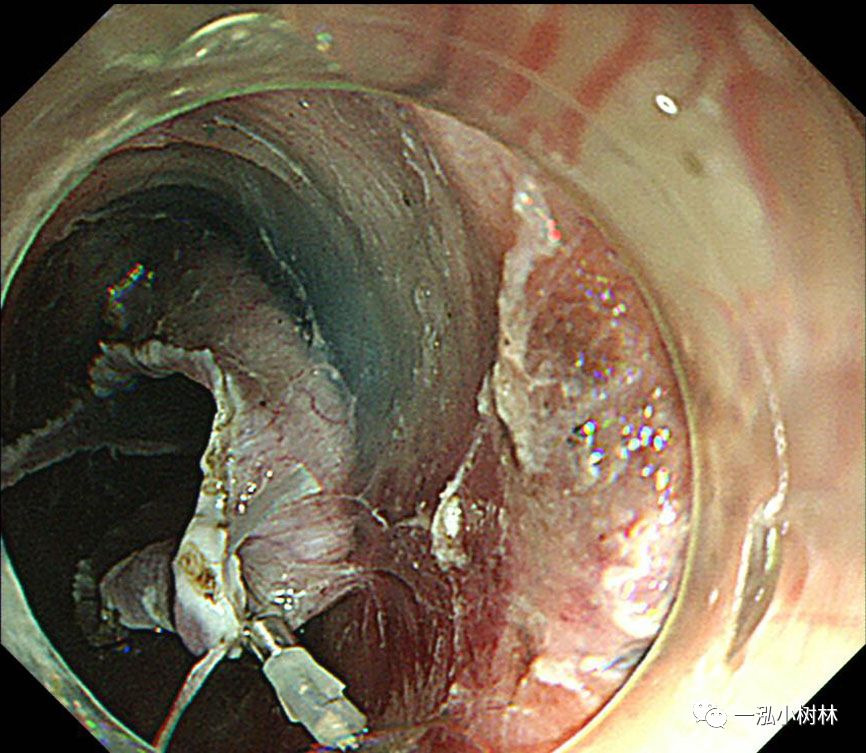

图7 使用IT刀进行纵向黏膜切口,并完成C形切口。

图8 行左侧黏膜下剥离术。在重力的作用下,黏膜剥离(左侧卧位行ESD)